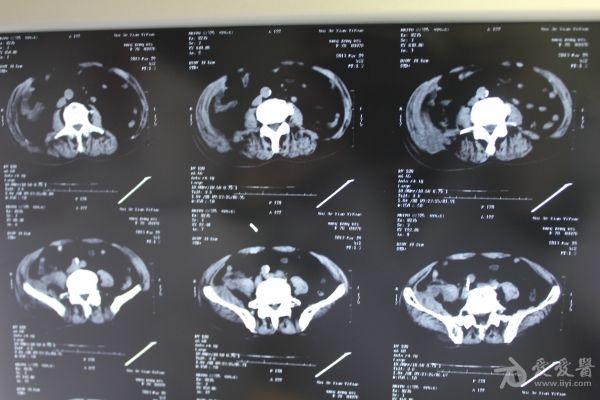

老年患者78岁,反复腰背部溃烂流脓4年,既往30年前曾在包块处排出蛔虫一条。CT:

明日手术探查